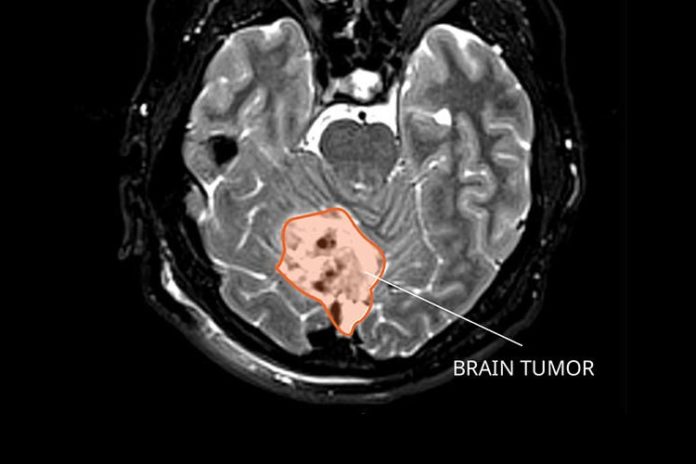

El meduloblastoma es el tumor cerebral infantil maligno más común y recientemente se ha clasificado en cuatro subtipos moleculares. Los tumores del grupo 1 tienen excelentes resultados en las terapias, rara vez se diseminan y rara vez son letales. Pero los grupos 2, 3 y 4 siguen siendo agresivos, tienen diseminación metastásica y son letales en el 20-30% de los pacientes a pesar del tratamiento completo.

El grupo 1 también se denomina subtipo Wnt, porque se caracteriza por la activación aparente de la vía de señalización Wnt, que es importante en múltiples tejidos y órganos durante el desarrollo normal. Una investigación realizada en el laboratorio de la Dra. Sheila Singh en la Universidad McMaster, publicada hoy en la revista Nature Communications, ha identificado un compuesto de molécula pequeña que puede activar la vía Wnt en subtipos de meduloblastoma no Wnt, lo que consigue que estas formas agresivas de cáncer respondan mejor a las terapias.